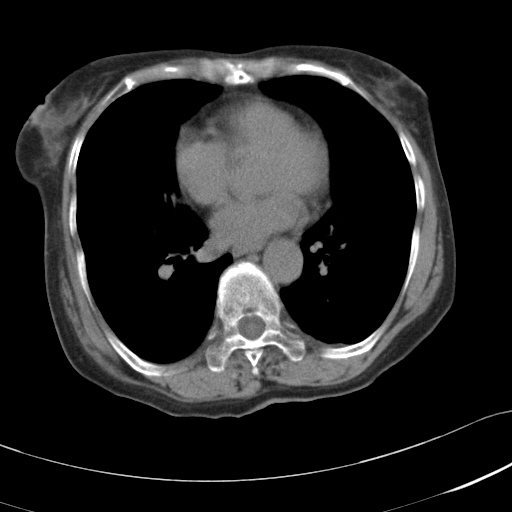

以下是引用hhcckk在2007-3-2 14:51:00的发言:[br]考虑结核球可能性大,依据[br]1病灶在下叶背段,结核的好发部位[br]2病灶内有大量的钙化,纵隔内有大量的淋巴结钙化[br]3重要的是半年前与现在相比无变化,假如是肿瘤的话不会这么‘善良’[br]4病灶周围卫星灶不明显,病灶有毛刺,胸膜凹陷,肿瘤不能完全排除,有条件的话最好做个活检